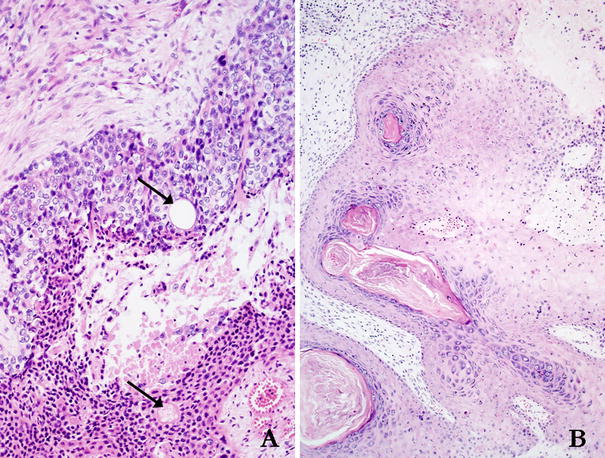

The patient underwent wide local excision of the mass and a left neck dissection of levels I–V. Surgical margins were achieved. On microscopic exam, the mass was consistent with an infiltrative carcinoma with clear cell morphology and focal squamous differentiation, with focal sebaceous differentiation and connection to a hair follicle, numerous duct-like structures, and myxoid stroma (Figs. 3 and 4). Immunohistochemical staining was grossly positive for HMW-cytokeratin (Fig. 5) and focally positive for CEA. CAM 5.2, CK7, CK20, S-100, TTF-1, and CDX2 were all negative. A final diagnosis of apocrine hidradenocarcinoma was made.

Fig. 4

a The tumor showed evidence of ductal differentiation with numerous patent ductal lumina (arrows). b In addition, areas of follicular differentiation were also apparent, as the tumor showed attachment to several follicular-cystic structures